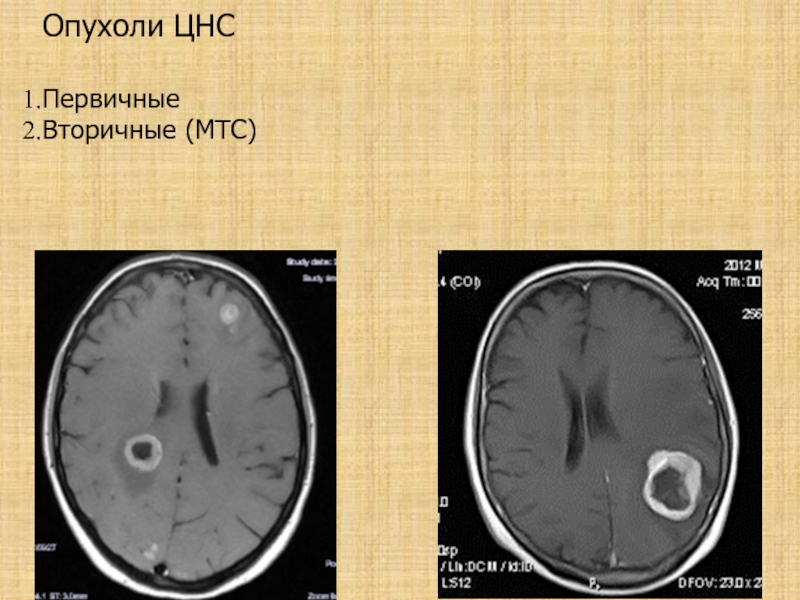

Слайд 6Опухоли ЦНС

Первичные

Вторичные (МТС)

Опухоли ЦНС Первичные Вторичные (МТС)